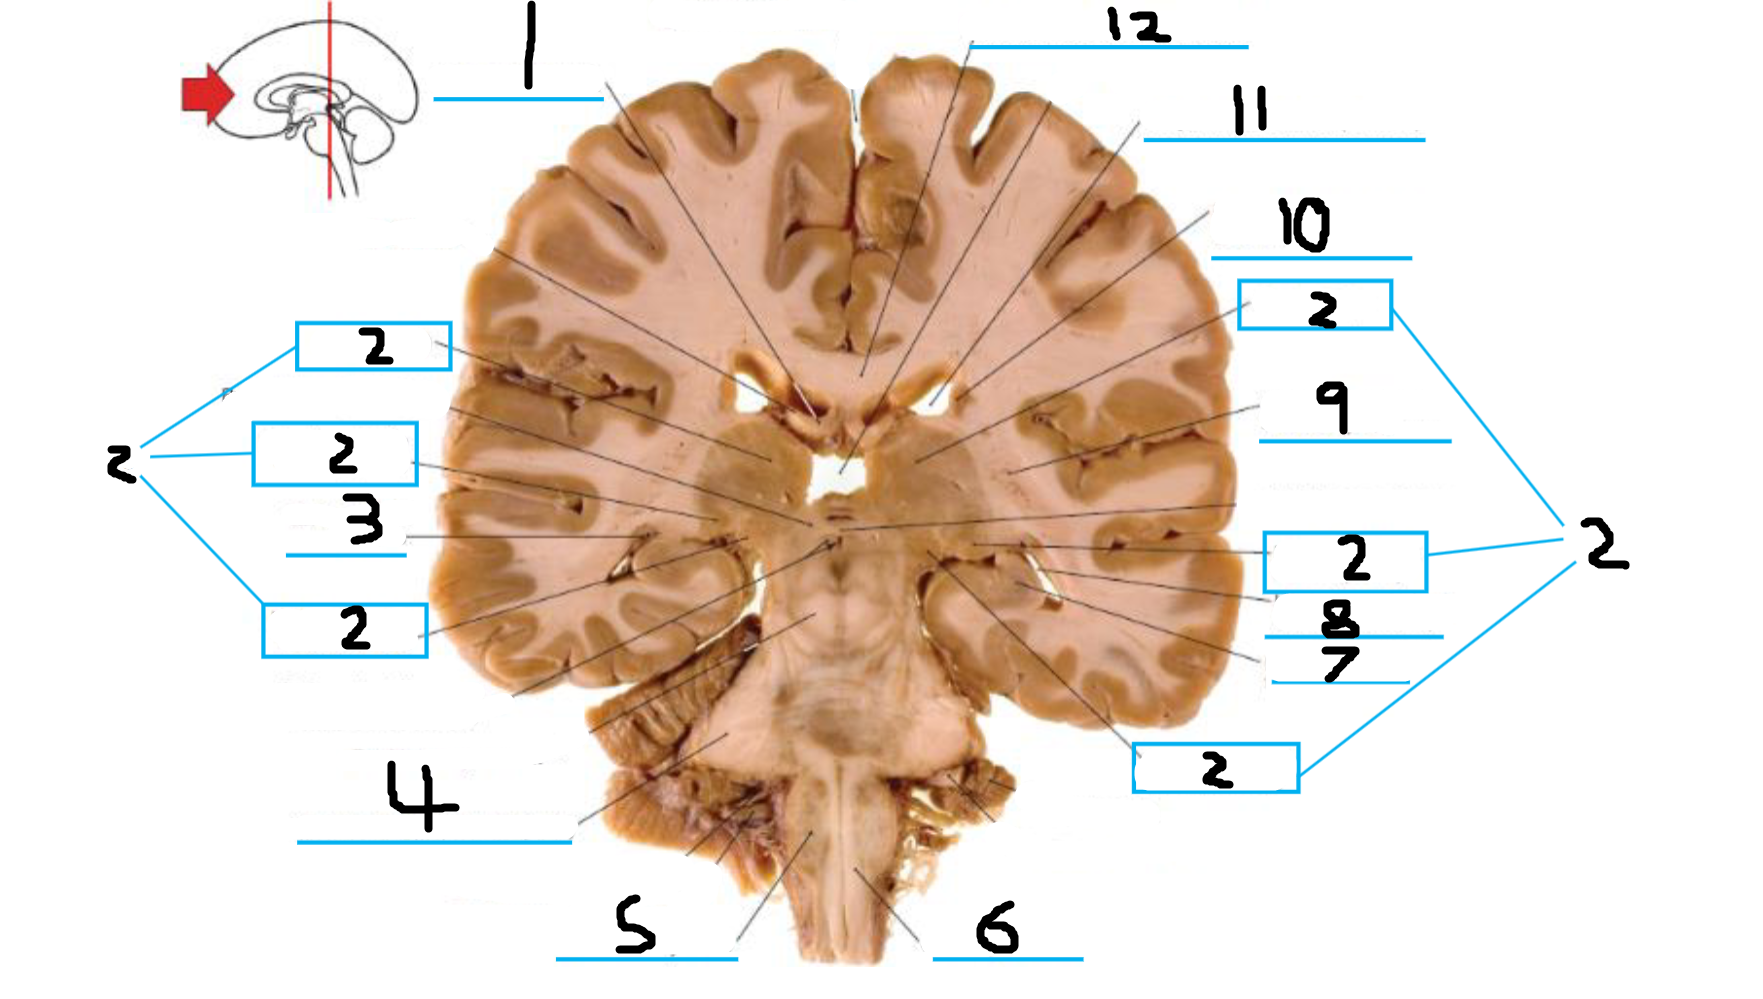

#3 and #16 are the:

Thalamus

#4 is the:

Hypothalamus

#5 and #9 is the:

Hippocampus

#6 is the:

Crus Cerebri

#7 is the:

Basilar Pons

#8 is the:

Mammillary Body

#10 is the:

Caudate

#11 is the:

Third Ventricle

#12 is the:

Globus Pallidus

#13 is the:

Insula

#14 is the

Putamen

#15 is the:

Internal Capsule

#17 is the:

#18 is the:

Lateral Ventricle

#19 is the:

Corpus Callosum